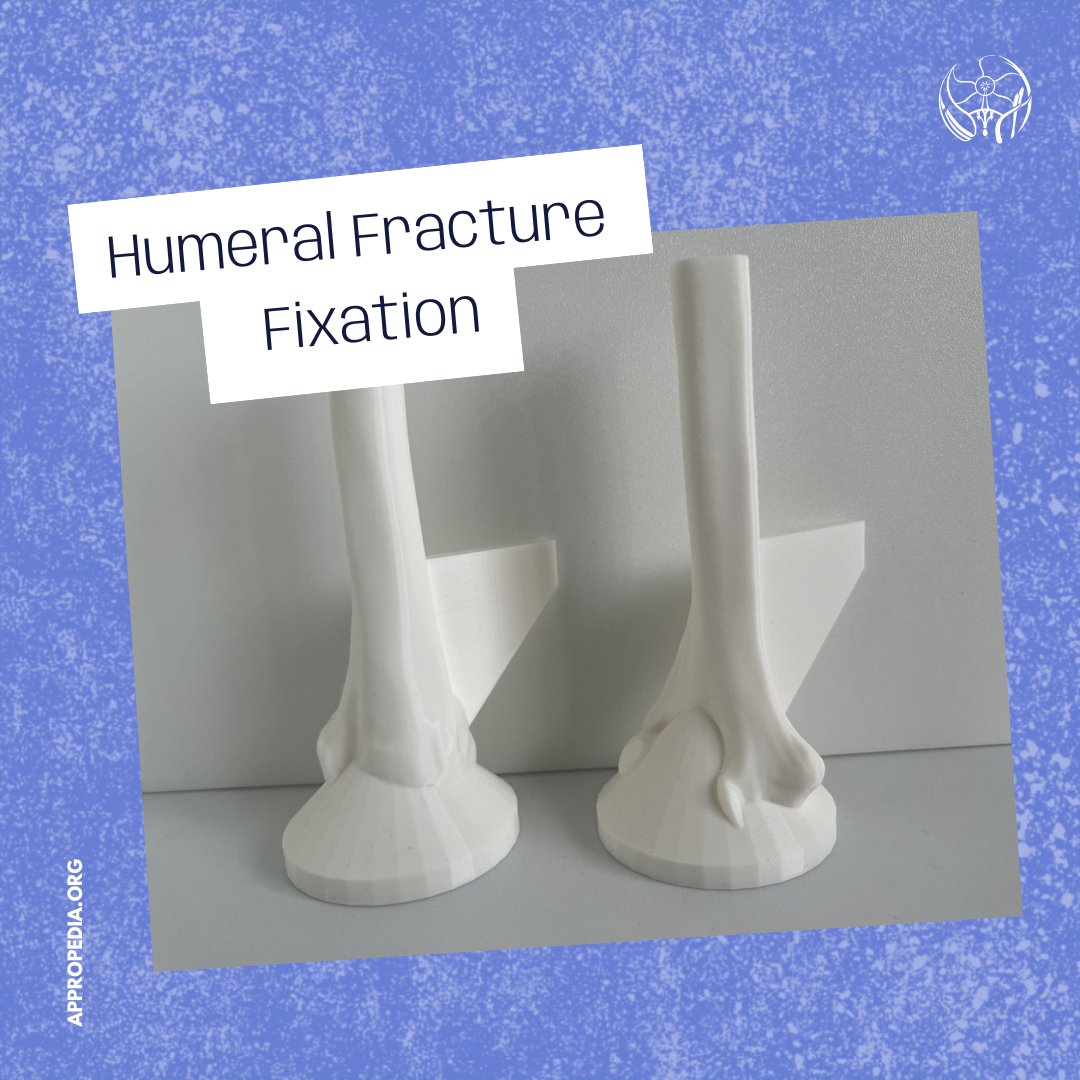

.Julielynn Wong and Habila Umaru set out to develop a module that teaches medical officers and non-orthopedic surgeons the essential surgical skills needed to treat tibial fractures. 💻 To learn more, visit appropedia.org/Tibial_Fractur… #GlobalSurgicalTrainingChallenge #RunnerUp